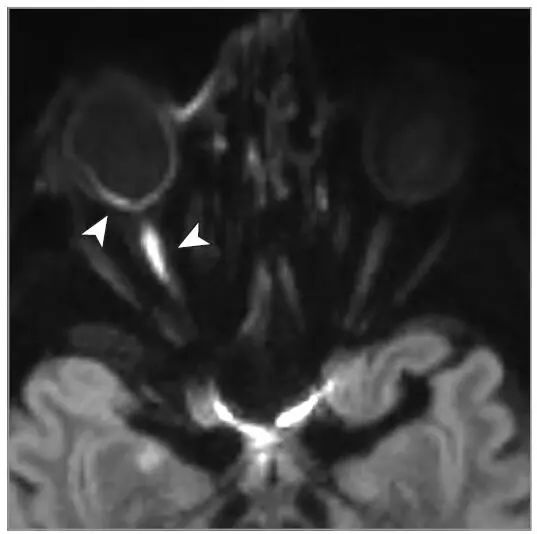

病史摘要:83 岁老年男性,因“前额疼痛性红斑性皮损持续一周”至急诊科就诊,初诊丹毒,口服克林霉素。一天后疼痛加剧,前额及左眼周围出现水疱性皮损,转诊眼科。患者曾因青光眼使用降眼压滴眼液。诊疗过程:眼部检查未见玻璃体或视网膜血管炎,Hutchinson 征阴性。诊断为眼带状疱疹(HZO),给予口服伐昔洛韦。次日出现复视,检查发现左眼内收等受限伴眼睑下垂。眼眶 MRI、脑 MRA 及